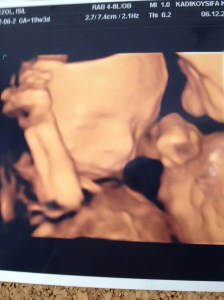

Sevgili doktorumun başını etini o kadar yedim ki, sonunda 18. haftada homurdana söylene, “Al işte, pipi yüzüyor !” dedi 😀 😀 Kutay’ın gözleri faltaşı gibi açılmış, ekrana bakıyordu gözlerini kırpmadan…”Hadi canım, emin misin yaa?” deyiverdi. “Gidin başımdan deliler !!!” cevabını alırken, benim suratımda azıcık gevrek bir sırıtış olduğunun farkındaydım.